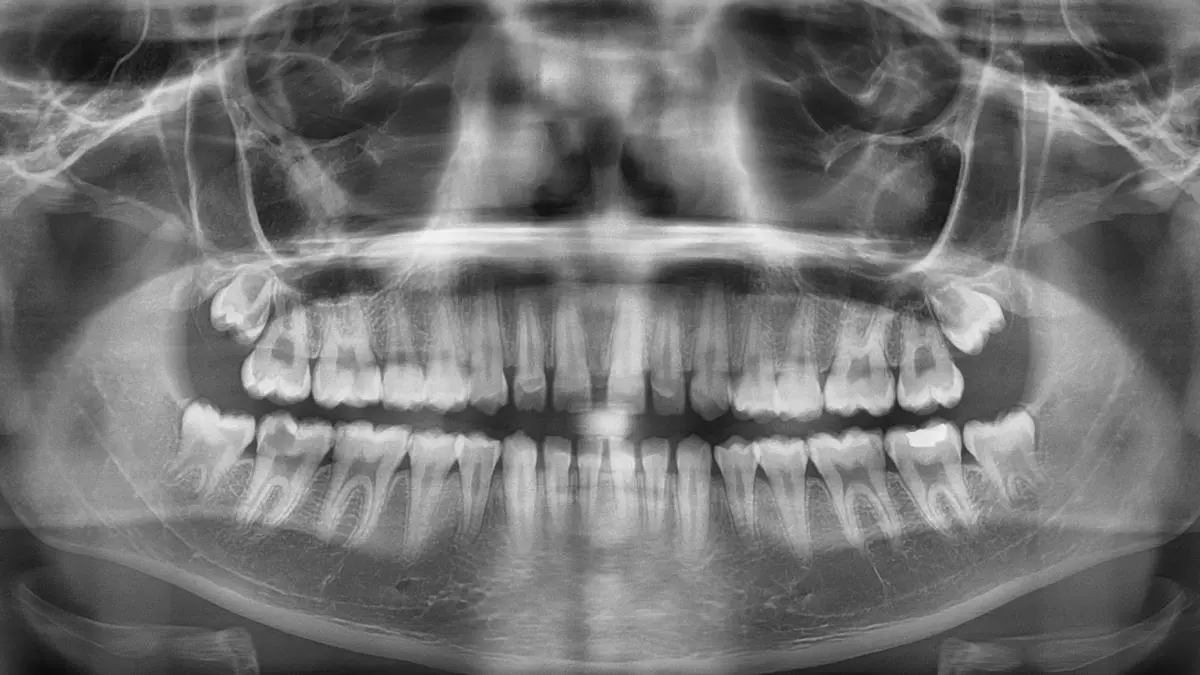

Radiografía dental utilizada en el trabajo. / UNIOVI

El modelo se entrenó con una muestra de 10.739 radiografías panorámicas dentales (ortopantomografías), de personas de 14 a 26 años, bien equilibrada entre hombres y mujeres, y procedentes de instituciones de doce países en cuatro continentes, "lo que garantiza la diversidad de la muestra y la robustez del sistema ante diferencias geográficas y biológicas". El método utiliza una red neuronal profunda denominada LAENet para estimar la edad de forma continua. Con este enfoque, el sistema obtuvo un error medio absoluto de solo 1,12 años, y una precisión del 88,38% al determinar si una persona supera o no el umbral de los 18 años.